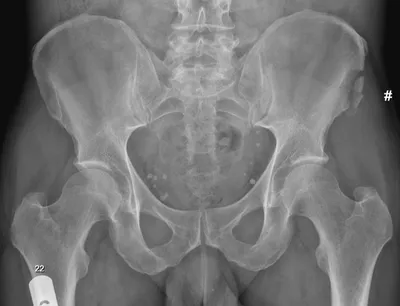

Avulsion Radiology Images

This collection contains 1 radiology images related to avulsion, including various imaging modalities such as X-rays, MRIs, CT scans, and ultrasound images commonly used in medical diagnosis and education.